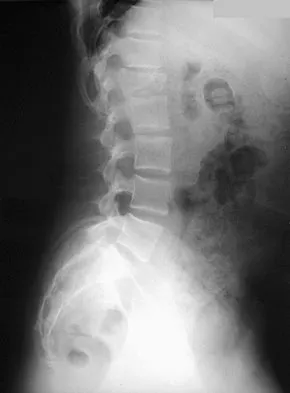

A 12-year-old girl has had lower back pain for the past 6 months that interferes with her ability to participate in sports. She denies any history of radicular symptoms, sensory changes, or bowel or bladder dysfunction. Examination reveals a shuffling gait, restriction of forward bending, and tight hamstrings. Radiographs show a grade III spondylolisthesis of L5 on S1, with a slip angle of 20 degrees. Management should consist of

Indications for surgical treatment of spondylolisthesis include pain and/or progression of deformity. Specifically, surgery is necessary when there is persistent pain or a neurologic deficit that fails to respond to nonsurgical therapy, there is significant slip progression, or the slip is greater than 50%. For patients with mild spondylolisthesis, in situ posterolateral L5-S1 fusion is adequate. In patients with more severe slips (greater than 50%), extension of the fusion to L4 offers better mechanical advantage. Postoperative immobilization may be achieved with instrumentation, casting, or both. In patients with a slip angle of greater than 45 degrees, reduction of the lumbosacral kyphosis with instrumentation or casting is desirable to prevent slip progression. Laminectomy alone is contraindicated in a child. Nerve root decompression is indicated if radiculopathy is present clinically. Seitsalo S, Osterman K, Hyvarinen H, Tallroth K, Schlenzka D, Poussa M: Progression of spondylolisthesis in children and adolescents: A long-term follow-up of 272 patients. Spine 1991;16:417-421.